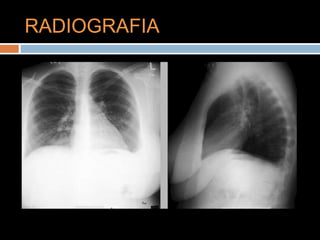

RADIOGRAFIA

LABORATORIOS Hemograma: Normal F. Renal:Normal Electrolitos normales Tiempos de coagulación normales. Dimero D: 850 VN: 0 – 500 Troponina: 0.295 Vn: 0 – 0.3

GASES ARTERIALES FIO2: 21% PH:7.47 PCO2: 32 PO2: 57 HCO3: 25 SAT: 87%